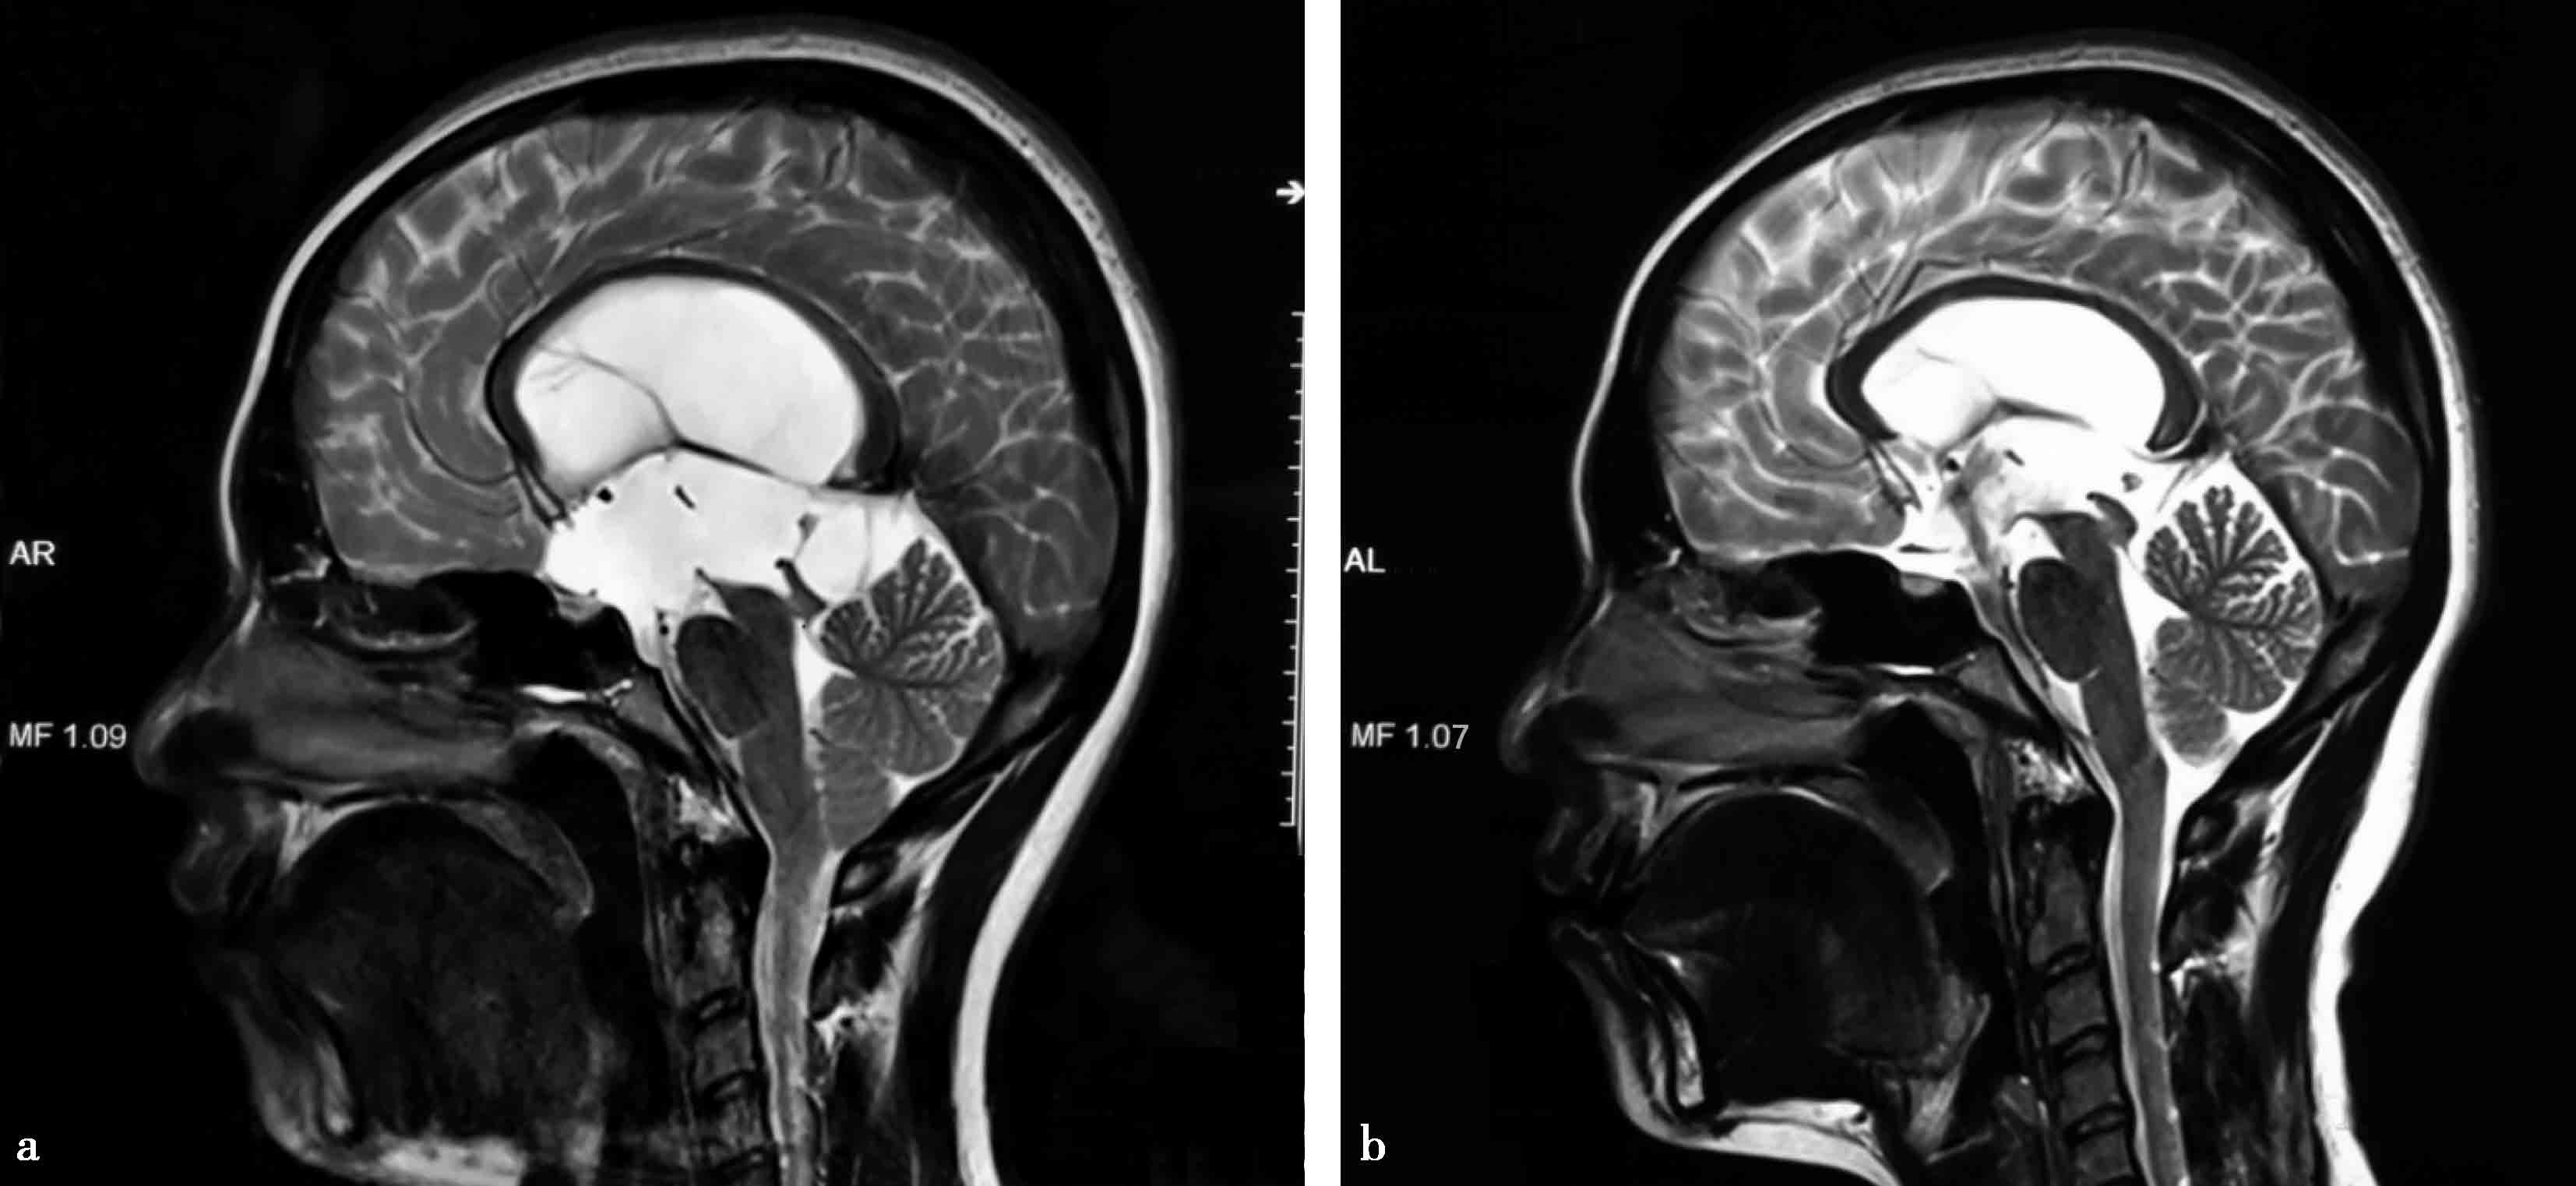

图3-1-1-2 第三脑室底下疝的神经影

a.头颅MRI矢状位片所见,酷似鞍上池囊肿;b.内镜下探查,证实长期脑积水所致第三脑室底深度下疝